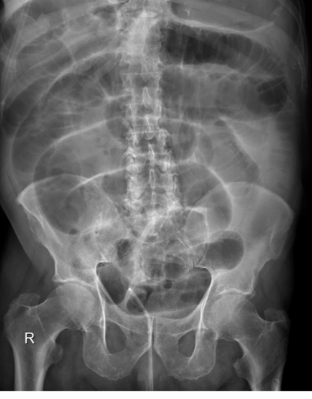

This abdominal X-ray shows multiple loops of dilated bowel with a loss of bowel markings **indicating large bowel obstruction. **